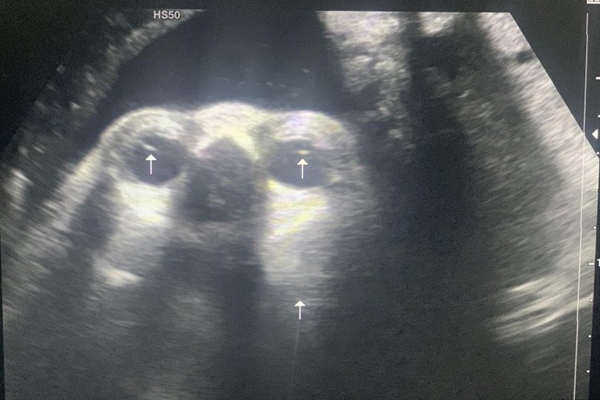

(Hình minh họa).